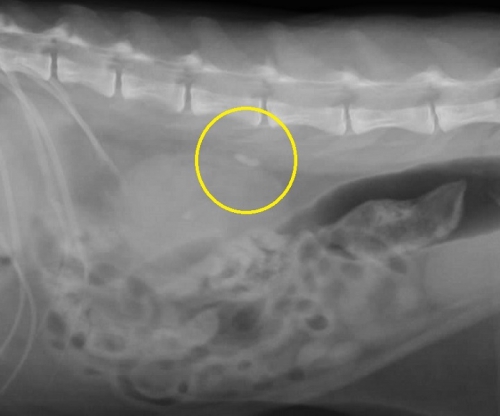

レントゲン検査により腎臓や尿管に結石が見つかった場合、さらに超音波検査によって結石の正確な位置関係とそれが周囲に及ぼす影響を評価します。下の2枚の写真は超音波検査の画像です。尿は左から右写真方向に「黒い管」として見える腎盂~尿管の中を流れます。

右下写真の黄色い円の中に見える「白いカタマリ」が尿管結石で、おおよそ3ミリくらいの直径があり、尿管を閉塞しています。

腎臓でつくられた尿がつまっているために尿管は重度に拡張しており、結石のすぐ上流で直径が4mm(赤矢印)、さらに腎臓の出口付近では1cm以上(緑矢印)にもなっており、腎臓内が拡張した水腎症になってしまっています。

通常では猫の尿管は極めて細いため超音波検査ではほぼ見ることができませんので閉塞の程度をイメージできるのではと思います。